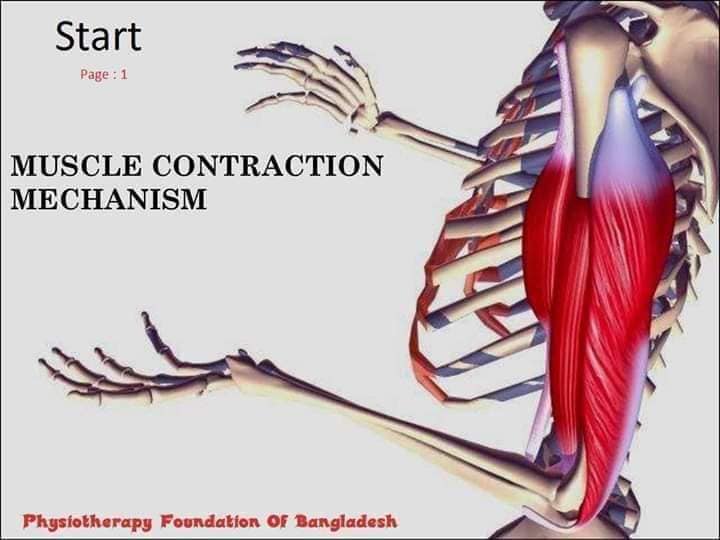

Скелетні м'язи з'єднані з кістками за допомогою сухожиль і відповідають за більшість волевих рухів. Вони поділяються на:

- Швидкі м'язи - призначені для швидких і потужних рухів.

- Повільні м'язи - забезпечують стійкі і довготривалі рухи.

Скелетні м'язи мають поперечну смугасту структуру, що забезпечує їхню здатність до швидкого і ефективного скорочення.